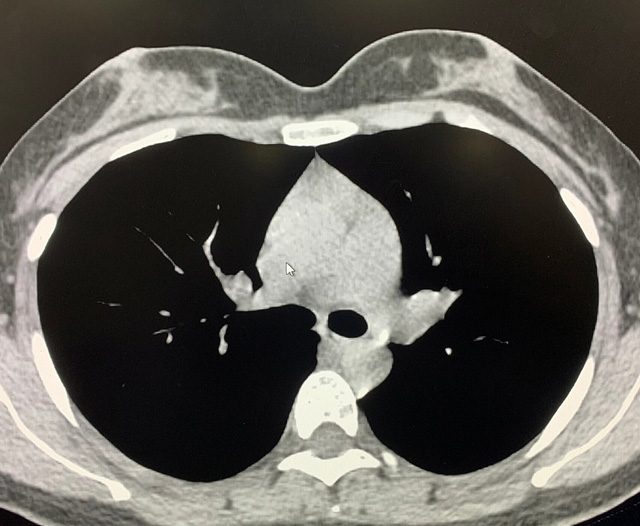

能譜純化技術(shù)的核心是通過物理濾過(如錫濾片)或軟件算法,選擇性濾除低能X射線光子,保留高能光子。在胸部低劑量CT掃描中顯著提升了圖像質(zhì)量與輻射劑量的平衡。

優(yōu)勢輻射劑量顯著降低相較于常規(guī)CT,輻射劑量減少約70%-90%,尤其適合需多次隨訪的高危人群(如肺癌篩查),降低輻射相關(guān)癌癥風(fēng)險(xiǎn)早期肺癌篩查效果明確可清晰檢測毫米級(jí)肺結(jié)節(jié),顯著提高早期肺癌檢出率,降低死亡率。檢查快捷且普及性高單次掃描僅需數(shù)秒,無需對(duì)比劑,設(shè)備廣泛配置于基層醫(yī)院,便于大規(guī)模篩查。長期成本效益顯著雖單次費(fèi)用與常規(guī)CT相近,但早期干預(yù)可大幅降低晚期治療費(fèi)用及社會(huì)醫(yī)療負(fù)擔(dān)。技術(shù)優(yōu)化提升圖像質(zhì)量迭代重建算法(如ASIR、MBIR)在降低劑量同時(shí)減少噪聲,平衡影像質(zhì)量與安全性。